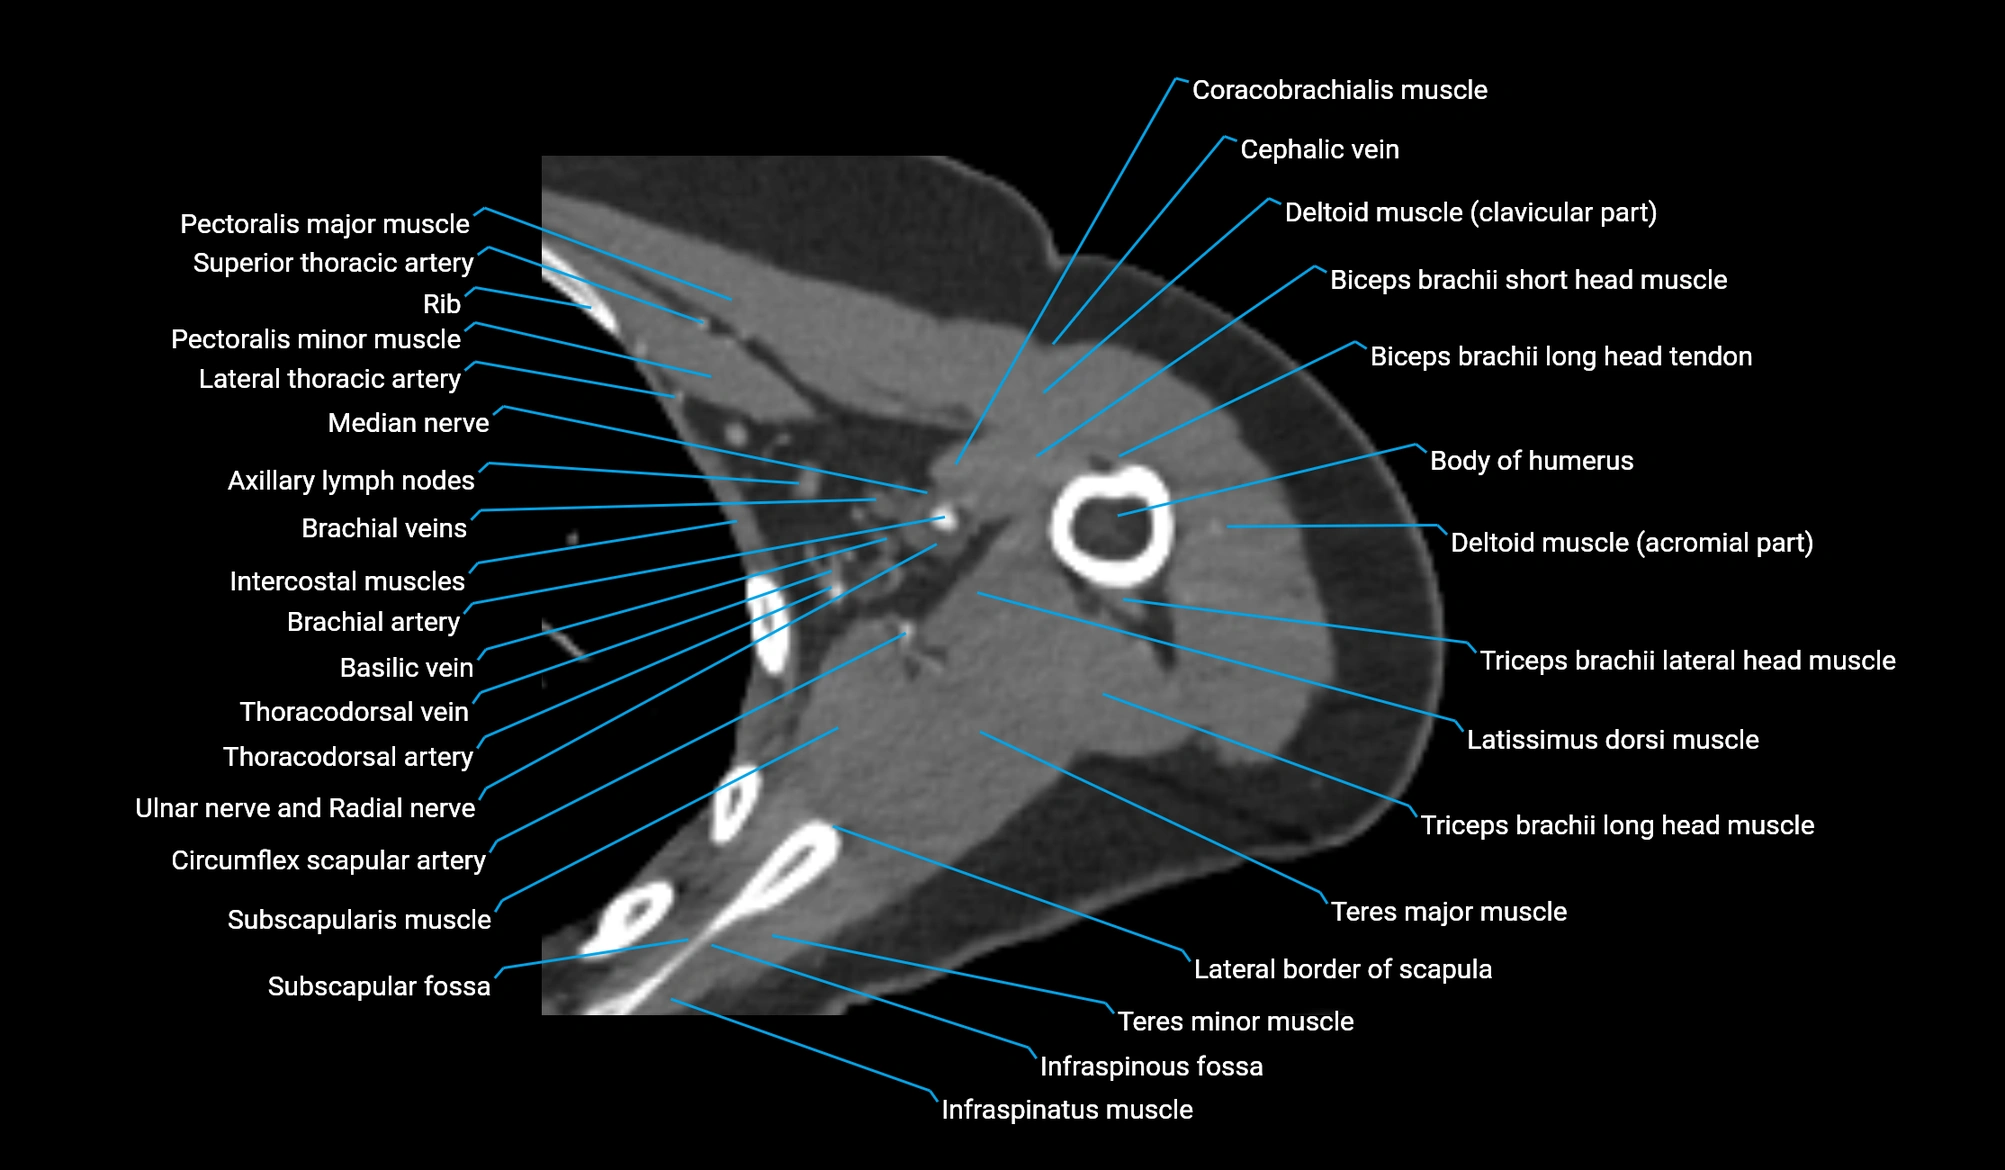

- Axillary lymph nodes

- Brachial artery

- Cephalic vein

- Circumflex scapular artery

- Clavicular part of deltoid muscle

- Coracobrachialis muscle

- Deltoid muscle

- Infraspinatus muscle

- Infraspinous fossa

- Lateral border of scapula

- Lateral head of triceps brachii muscle

- Latissimus dorsi tendon

- Long head of triceps brachii muscle

- Median nerve

- Pectoralis major muscle

- Pectoralis minor muscle

- Subscapularis muscle

- Subscapular fossa

- Teres major muscle

- Teres minor muscle

- Thoracodorsal artery

- Triceps brachii muscle